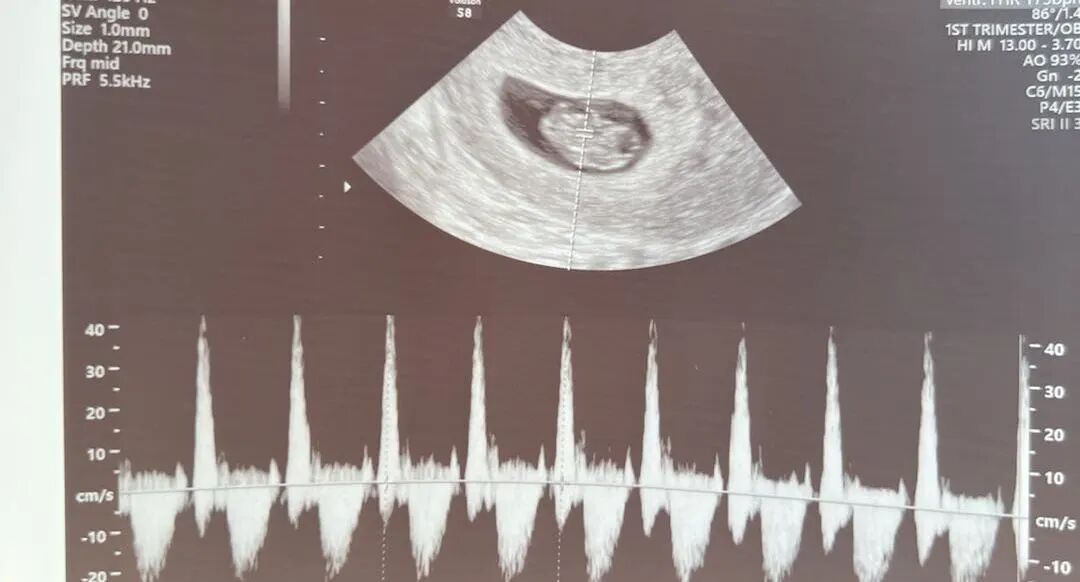

在怀孕八周时,胚胎进入了关键的发展阶段,体长约1.6厘米,已经开始显示复杂的生理特征和明显的人类形态。这个时期,胚胎的大脑结构如脑室和脑裂开始形成,基础心脏也已经开始跳动,并将分为两个房室,已经可以听到宝宝强壮有力的心跳声了。恭喜我们的准爸爸,我们都非常期待在接下来的检查中看到宝宝更多的成长和发展情况。

爱妈D已经怀孕11周了,她即将从诊所“毕业”。从匹配成功开始,爱妈D就表现出了极高的配合度,赢得了准父母的深厚喜爱。这次又迎来了宝宝已经顺利着床的好消息。听到了宝宝强健的心跳声,宝宝正在健康地成长。我们满怀期待地希望宝宝能继续顺利成长!